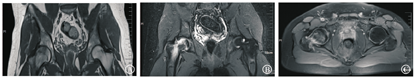

左髋痊愈后约4个月该患者又于2019年1月无明显诱因出现右髋疼痛而就诊,症见右侧腹股沟、大腿前方钝痛,跛行,刺痛为主,痛处不移。查体发现腹股沟压痛明显,关节活动受限,抗痛性步态。舌暗,可见瘀点,苔薄白,脉细涩。症状体征与左髋发病时基本相同,行双侧髋关节MRI检查见:右侧股骨头颈、股骨粗隆及股骨上段骨髓水肿,左侧股骨头颈部少许骨髓水肿。右侧髋关节积液(图4)。结合病史、症状、体征亦考虑为BMES,四诊合参属于中医"骨痹"范畴,气滞血瘀为主,同时兼夹痰湿、肝肾亏虚。